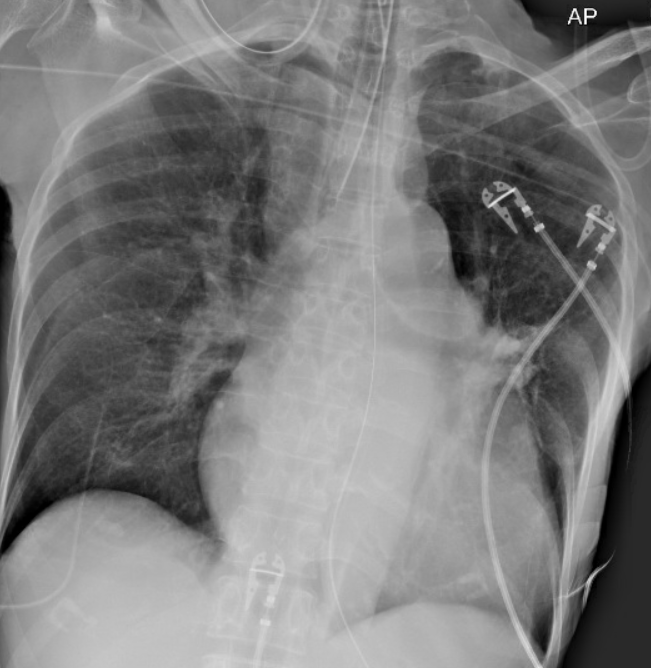

Chest Xray with EKG before and after gradual rewarming:

-No pleural effusions, suggestion of hilar vessel enlargement